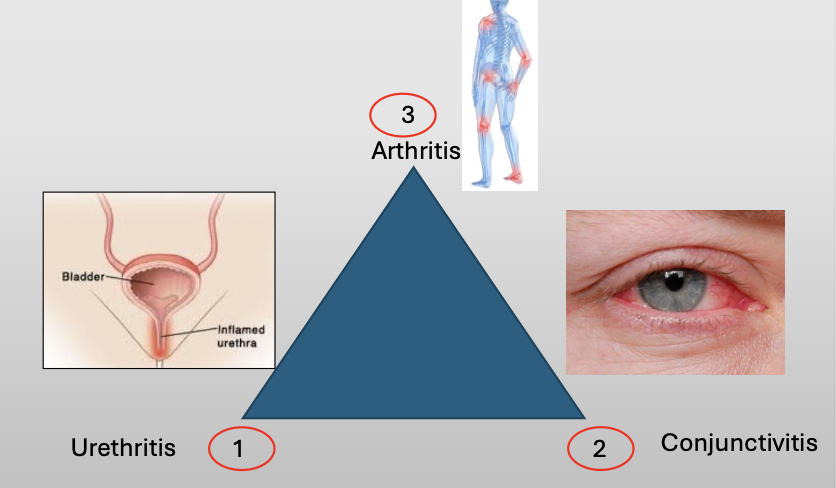

What is another name for reactive arthritis

Reiter Syndrome

What is Reiter Syndrome?

A chronic disease that classically compromises a triad of three featuers:

Urethritis

Conjunctivitis

Arthritis

What is the cause of Reiter Syndrome?

Unknown, 10% have HLA-B27

Oral lesions are 20% (nonspecific)

NSAID/AB if infection/steroids

What demographic does Reiter Syndrome show up in?

M:F (9:1)